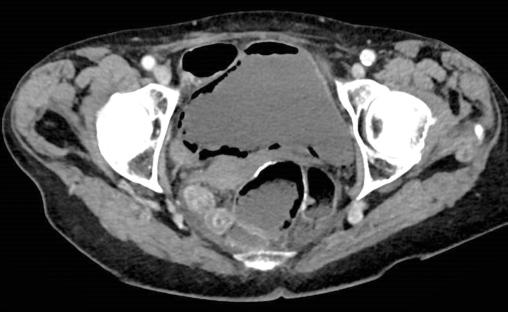

Cystite emphysémateuse

2. Cystite emphysémateuse